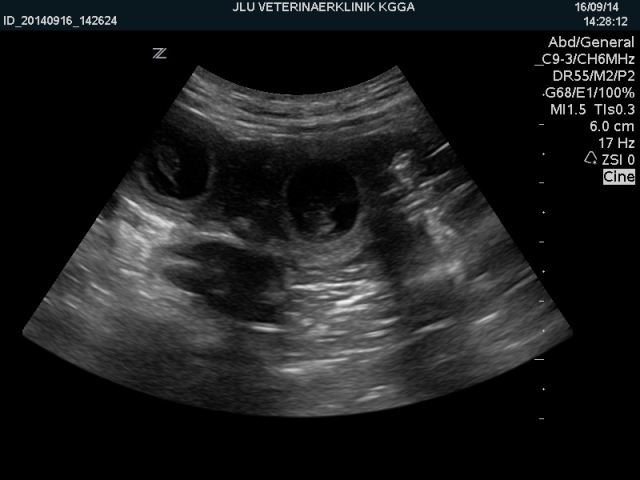

16. September - 25. Tag

Jiiiippiiiii :)

Joe bekommt viele kleine I-dötzchen :) :)

Wieviele kann man beim Ultraschall ja nie sagen, aber bei dem kurzen Blick in ihren Bauch

konnten Franzi und ich viele kleine Fruchthüllen mit I-dötzchen und schlagenden Herzen sehen.

Sie lagen dicht beieinander, das ist immer ein gutes Zeichen für ein gefülltes Bäuchlein :) :)

Juhuu!!!

Auf dieser Vergrößerung kann man schön sehen, wie der kleine Schatz in seiner

Fruchthülle liegt, durch die Nabelschnur mit Joe verbunden :)

Einfach wunderbar..